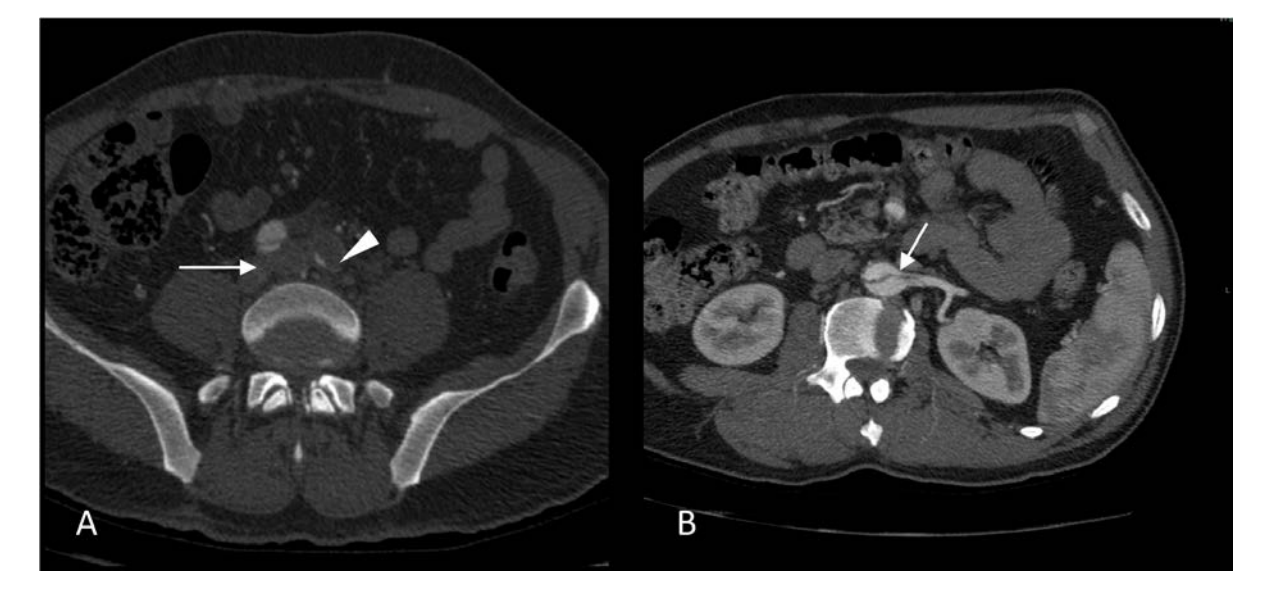

Coronary angiography (CA) was performed 24 hours after admission, an intermediate stenosis was found in the left anterior descending artery (LAD) with TIMI 3 flow (Figure 2). Ventriculography showed mild anteroseptal hypokinesia with a 60% left ventricular ejection fraction (LVEF). Aortic root dilation was observed along with a double contour image suggestive of aortic dissection (Figure 3). Aortic CT was then performed, the study revealed an aortic dissection extending through the thoracic, abdominal and common iliac arteries, classified as a Type A aortic dissection (Figures 4-6). CT angiography 3D reconstruction showed a dissection originating at the aortic root that involved the innominate, left subclavian and left vertebral arteries as well as the descending aorta and extended through the entire course of the common iliac artery causing left iliac artery occlusion (Figure 7).